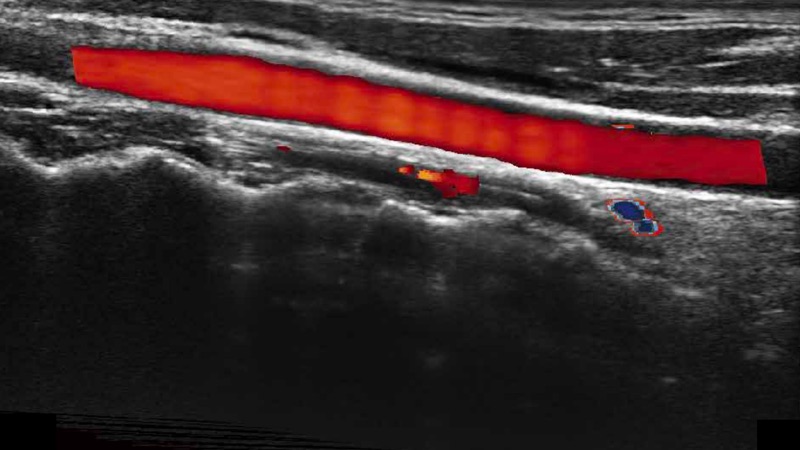

通過(guò)色彩血流和實(shí)時(shí)寬景相結(jié)合,可觀察到完整的靜脈或動(dòng)脈的血流,方便醫(yī)生檢查。實(shí)時(shí)掃查過(guò)程中,如有任何操作失誤也可以很容易地進(jìn)行回掃擦除,而不會(huì)中斷掃查。

自動(dòng)識(shí)別前后壁內(nèi)膜厚度,為心血管疾病早期評(píng)估提供快速準(zhǔn)確依據(jù)。